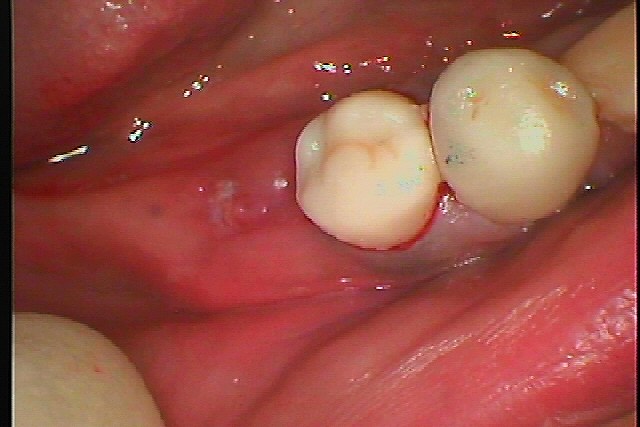

とのことで6番だけインプラントを埋入していきます

インプラント埋入時になります

骨補填材を転入して縫合して終了となります